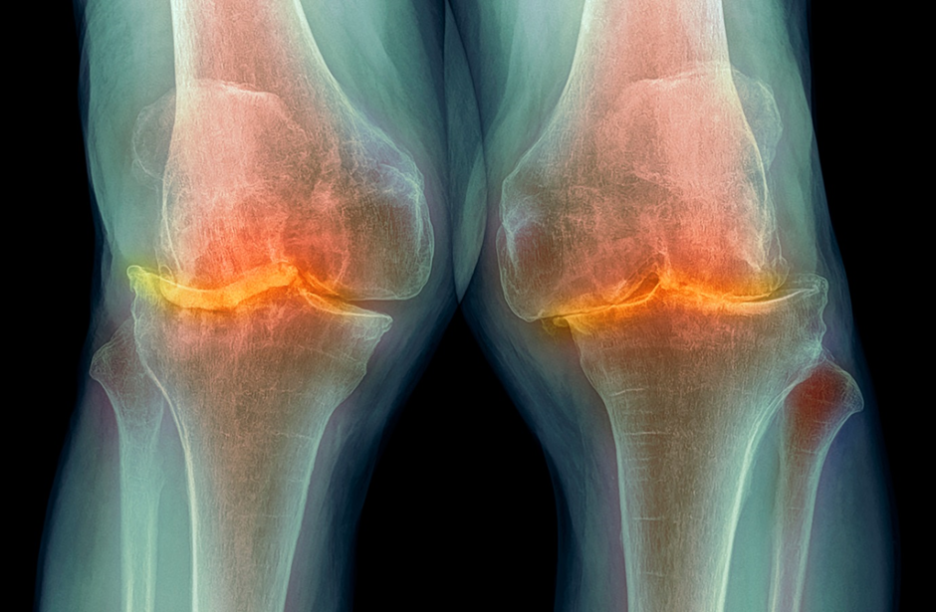

천호정형외과 무릎 연골 통증과 뻐근한 증상 천호정형외과 : 무릎은 인체에서 가장 중요한 관절 중 하나로서 일상 생활에서 많은 활동에 사용됩니다. […]

강일역정형외과에서 무릎 연골 통증과 뻐근한 증상을 해결하세요 무릎 연골 통증은 일상생활에서 흔히 겪는 문제 중 하나로, **강일역정형외과**에서 전문적인 치료를 받을

강동구정형외과에서 추천하는 무릎 접을 때 통증과 쑤심 치료 무릎 관절은 일상생활에서 가장 많이 사용되는 관절 중 하나로, 접을 때 통증과

강동구정형외과에서 추천하는 무릎 통증 및 쑤심 치료 방법 무릎 접을 때 통증과 쑤시는 고민을 가지고 계신가요? 무릎 관절 부위는 우리